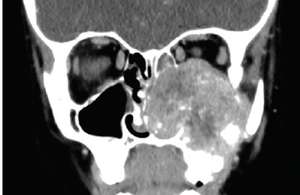

A 6-year-old boy presented to his pediatrician with clear drainage from his left eye for 1 to 2 days. He denied itchiness, pain, vision changes, nasal congestion, or history of allergies. What's the diagnosis?